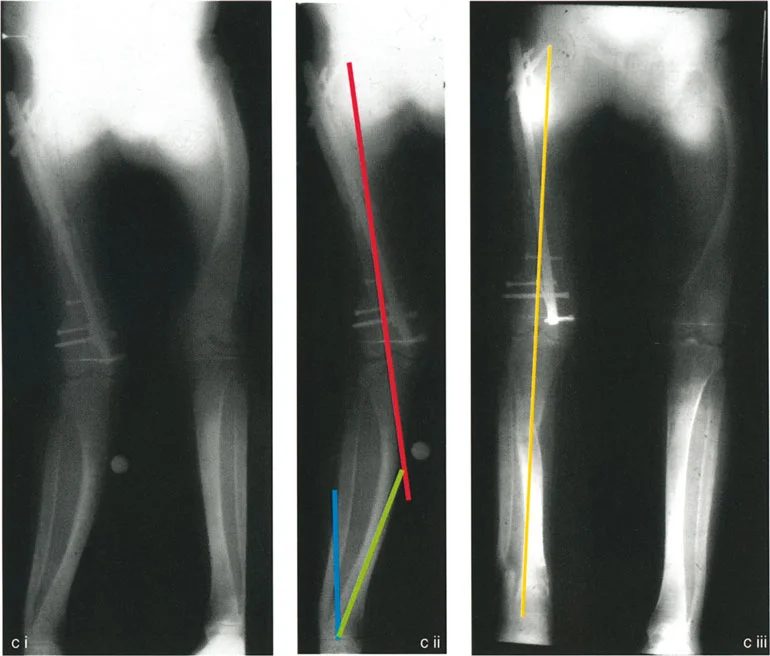

بالنسبة للمرضى الذين يعانون من تشوهات معقدة، خاصة تلك التي تؤثر على عظم الساق (الظنبوب) وتظهر على شكل انحناءات متعددة المستويات، فإن فهم هذه التعقيدات أمر بالغ الأهمية. هذه الحالات غالبًا ما تتطلب أكثر من مجرد تدخل جراحي بسيط؛ فهي تتطلب خبرة جراح ماهر يفهم لماذا تفشل عمليات قطع العظم أحادية المستوى في مواجهة التقوسات الشاملة أو الانحرافات الزاوية المعقدة متعددة المستويات.

من خلال هذا الدليل الشامل، سنسلط الضوء على الميكانيكا الحيوية الكامنة وراء حلول قطع العظم أحادية مقابل متعددة المستويات، ونكشف عن المخاطر الخفية في تصحيح التشوهات، مثل الكشف غير المقصود عن مفصل ذي اتجاه خاطئ. في صنعاء، يقود الأستاذ الدكتور محمد هطيف، استشاري جراحة العظام والعمود الفقري، هذا المجال بفضل خبرته الواسعة وتطبيقه لأحدث التقنيات العالمية في تشخيص وعلاج انحرافات الساقين المعقدة، مما يجعله المرجع الأول للمرضى الباحثين عن حلول متقدمة ودقيقة.

2. الأشعة السينية الطويلة الكاملة مع تحمل الوزن (Full-length, Weight-bearing Radiographs)

هذه هي الأداة التشخيصية الأكثر أهمية. يتم التقاط صورة شعاعية واحدة تم